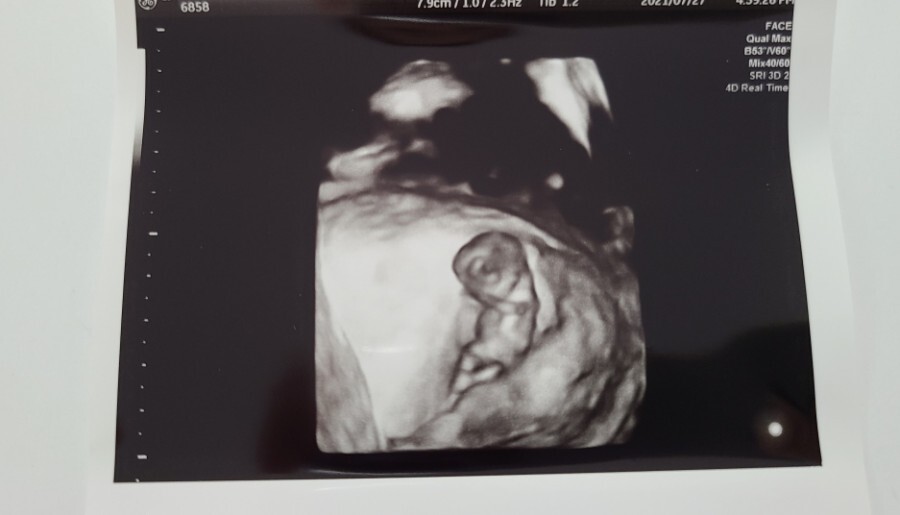

10주 차부터는 보통 질 초음파가 아닌 복부 초음파로 아기의 상태를 확인할 수 있다고 하셔서 복부 초음파로 아기의 상태를 확인했어요.

복부 초음파로 확인한 우리 아기의 크기는 3.45cm로 주수에 맞게 잘 크고 있다고 하시더라고요.

심장 소리도 지난번보다 더 우렁차졌다고 하셔서 조금은 안심할 수 있었고 이젠 제법 사람의 형태가 보이는 것 같아 신기하기도 했어요.